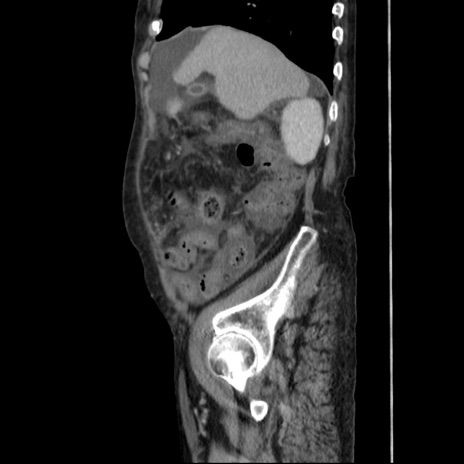

症例31(矢状断像)

【症例】80歳代 女性

【主訴】腹部膨満感

【現病歴】他院にて肝硬変にてフォロー中。1週間前から便秘、腹部膨満感、臍部腫瘤あり受診となる。

【既往歴】肝硬変

【身体所見】腹部膨隆あり、皮膚変化なし、疼痛なし。

【データ】WBC 4600、CRP 0.25